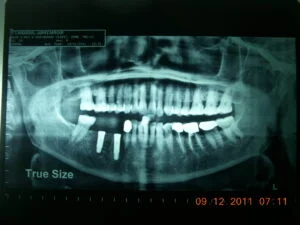

Clinical Case Progression

Full Mouth Rehabilitation

Implant Supported Fixed Teeth

Replacing all missing teeth with a permanent, fixed prosthesis that mimics the look, feel, and function of natural teeth. Explore our clinical transformations below.